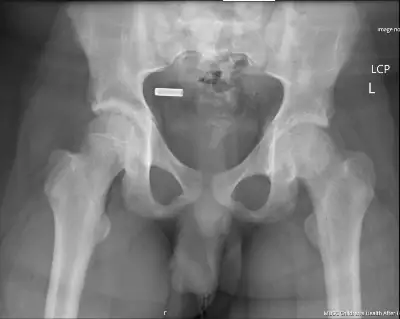

The PED team repeated radiographs of the bilateral hips (Figure 2) with better penetration that confirmed the diagnosis of SCFE. The orthopedic service was consulted and recommended open reduction and internal fixation to repair the slip in an attempt to prevent avascular necrosis. He was admitted to the hospital under the orthopedic service, made non-weight-bearing status, and ordered nothing by mouth at midnight. He had labs drawn for thyroid stimulating hormone and vitamin D levels that were within normal limits. He was taken to the operating room the next morning and discharged home the same day following the procedure. After the surgery, he had 2 follow-up visits with orthopedics and was doing well.

When there is an appropriate degree of suspicion for SCFE, the next step is to obtain radiographs. Several images are important to aid in the diagnosis including an AP view of the affected hip and the pelvis to compare both sides, as well as a frog-leg lateral view of the affected side. The severity of the slip is related to the stability, chronicity, and degree of slip. A stable slip is defined as a patient that is able to bear weight on the affected limb and walk with or without an assist device—as opposed to an unstable slip, which is defined as a patient who cannot walk in any capacity.[8] Acute versus chronic is defined as the presence of symptoms less than or more than 3 weeks in duration, respectively. Acute-on-chronic is defined as greater than 3 weeks overall with acute worsening of symptoms.4 The degree of the slip is split into 4 categories: pre-slip; mild; moderate; and severe, which can be determined based on the calculated Southwick angle (the angle between the epiphyseal and diaphyseal axes) on the radiographs. Pre-slip occurs when there is a widening of the physis but no displacement of the epiphysis. Mild slips start at <30° of difference between the affected and normal side; moderate is 30°–50°; and severe is >50°.